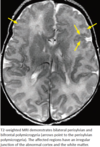

- On MR imaging, sulci appear thick, bumpy, small, and irregular. The junction of the polymicrogyric cortex and the white matter is irregular and less well defined than normal.

- Bilateral perisylvian polymicrogyria is the most common distribution.